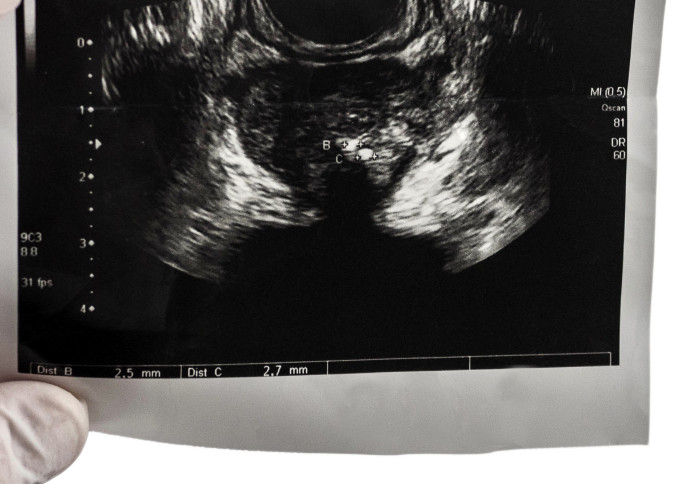

В свою очередь в этом исследовании применялся метод мультипараметрического УЗИ (mpUSS), который использует звуковые волны для просмотра простаты. В исследовании применялся зонд, который помещался в прямую кишку и посылал звуковые волны, которые отражаются от органов и других структур. Затем эти сигналы превращаются в изображения органов. Врач, проводящий исследование, также использует дополнительные виды ультразвуковой визуализации, которые позволяют определить жесткость тканей и степень их кровоснабжения. Эти методы называются эластография, допплерография и микропузырьковое контрастное усиление. Поскольку раковые опухоли более плотные и снабжаются большим количеством крови, они проявляются более четко.